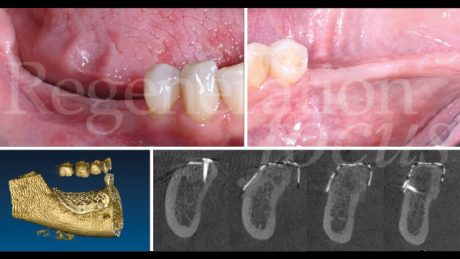

Il follow-up a 2 e 4 settimane ha documentato la guarigione per prima intenzione. A 6 mesi, la CBCT ha evidenziato eccellente integrazione dell’innesto con ottimale densità ossea (Fig. 10). La seconda fase chirurgica ha previsto la rimozione della mesh e l’inserimento simultaneo di due impianti tissue level (3.7 x 10 mm plat. 3.7 in sede 45; 3.7 x 8 mm plat. 4.5 in sede 47) caratterizzati da un design transmucoso concavo di 1.8 mm con superficie anodizzata (Matrix Line, TRI Dental Implants) (Fig. 11). Il torque di inserimento di 45 Ncm ha confermato l’ottima qualità ossea.

Durante la stessa seduta, valutato il sottile spessore mucoso, si è proceduto alla modificazione del fenotipo tissutale. Una matrice di collagene (Geistlich Fibro-Gide®) è stata posizionata con tecnica “a poncho”: la matrice è stata bucata in corrispondenza delle viti di guarigione degli impianti e posizionata sulla cresta alveolare, permettendo di ispessire il complesso dei tessuti molli sovracrestali sia verticalmente che orizzontalmente (Fig. 12).

Il periodo di osteointegrazione è trascorso senza complicanze (Fig. 13). A quattro mesi, l’impronta digitale con scanner intraorale ha registrato la morfologia dei tessuti molli maturati (Fig. 14). Le corone monolitiche in zirconia stratificata sono state progettate e realizzate (Odt. Antonio Corradini) con emergenza graduale per supportare i tessuti molli, sfruttando la connessione diretta delle corone protesiche senza l’utilizzo di monconi o cemento, eliminando micro-gap e micro-movimenti in grado di compromettere la stabilità del sigillo biologico (Fig. 15).

Il follow-up clinico e radiografico a 12 mesi ha documentato eccellente stabilità del risultato ottenuto. L’analisi radiografica non ha evidenziato rimodellamento osseo marginale né segni di radiolucenza peri-implantare o alterazioni della trabecolatura ossea (Fig. 16). I parametri clinici peri-implantari hanno mostrato profondità di sondaggio inferiori a 4 mm e assenza completa di sanguinamento al sondaggio. L’analisi del fenotipo tissutale ha documentato incremento significativo dello spessore mucoso e l’analisi del microbioma ha rivelato composizione batterica compatibile con la salute peri-implantare e il mantenimento dell’eubiosi (Figg. 17,18).